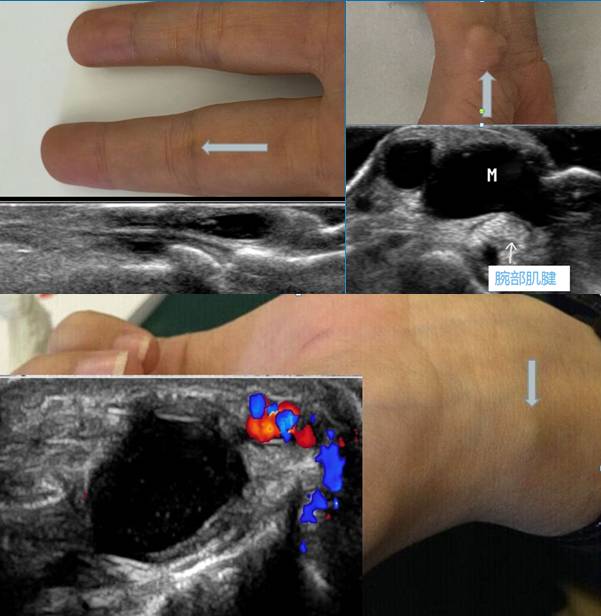

(1)手腕部腱鞘囊肿:多发生于腕背侧,少数在掌侧。最好发的部位是指总伸肌腱桡侧的腕关节背侧关节囊处,其次是桡侧腕屈肌腱和拇长展肌腱之间。腕管内的屈指肌腱鞘亦可发生囊肿,压迫正中神经,诱发腕管综合征。少数腱鞘囊肿可发生在掌指关节以远的手指屈肌腱鞘上,米粒大小,硬如软骨。

(2)足踝部腱鞘囊肿:以足背腱鞘囊肿较多见,多起源于足背动脉外侧的趾长伸肌腱腱鞘。跗管内的腱鞘囊肿可压迫胫神经,是跗管综合征的原因之一。

超声:一般表现为皮下层、与肌腱或关节关系密切的类圆形或不规则无回声结节,可单房,也可分隔,边界清楚,后壁回声增强,较大囊肿囊壁上可探及血流信号。